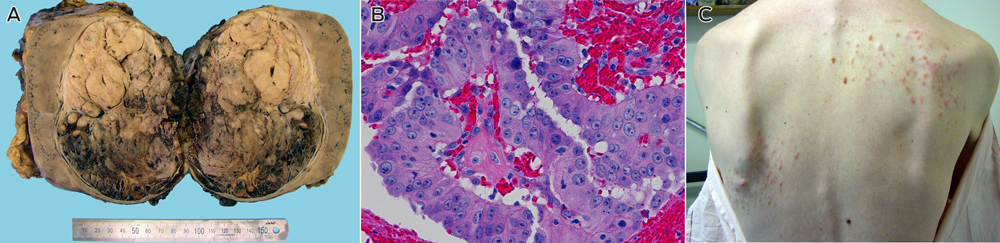

A 25-year-old white man presented with a year-long history of malaise, a palpable right loin mass and a painless nodular rash over his back of indeterminate duration. Computed tomography (CT) showed a right renal mass with para-aortic and retroperitoneal lymphadenopathy. The patient underwent radical nephrectomy and para-aortic lymphadenectomy.

Examination of the kidney showed a 14 cm tumour centred in the renal medulla (Box, A). The tumour cells were organised in papillary fronds and featured abundant eosinophilic cytoplasm, large nuclei and prominent inclusion-like eosinophilic nucleoli (Box, B). There was widespread vascular space invasion and involvement of the renal sinus fat and hilar vein. All four para-aortic lymph nodes contained metastatic disease.

The patient's longstanding skin rash (Box, C) was reviewed and confirmed on biopsy to represent multiple cutaneous leiomyomata.1 The patient's mother was found to have had multiple cutaneous and uterine leiomyomata. The death certificate of his maternal grandfather stated that he died of metastatic renal carcinoma at the age of 44. He had returned from active service in World War II with a mysterious and longstanding rash, the pattern of which was consistent with cutaneous leiomyomatosis. On this basis a provisional diagnosis of hereditary leiomyomatosis and renal cell cancer (HLRCC) was made.1